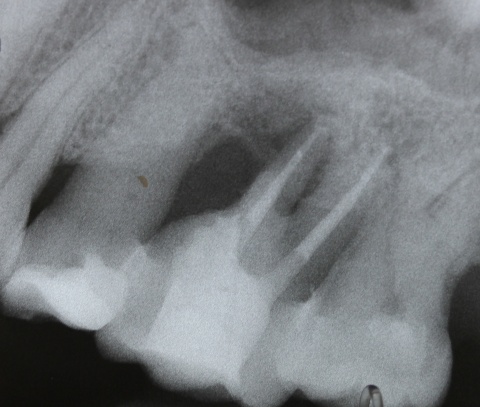

Durch eine Vielzahl von Studien konnte belegt werden, dass die Versorgung mit implantatgetragenem Zahnersatz eine bewährte Behandlungsoption darstellt. Gleichwohl zeigen viele Studien jedoch, dass – wie bei allen Therapiemaßnahmen auch – Komplikationen auftreten können. Diese haben im Allgemeinen biologische oder technische Ursachen. Als häufigste biologische Komplikation findet man die Mucositis (Abb. 1), die Entzündung der periimplantären Gewebe ohne Beteiligung des Alveolarknochens. Nach aktuellen Studien weisen ca. 30 % aller Implantate nach fünf Jahren eine Mucositis auf. Kommt es darüber hinaus zu einer Beteiligung des Alveolarknochens, liegt eine Periimplantitis vor (Abb. 2). Sie tritt nach fünf Jahren bei etwa 10 % der inkorporierten Implantate auf und ist durch den Verlust des periimplantären Alveolarknochens gekennzeichnet. Die Periimplantitis kann, je nach Schweregrad, zum kompletten Implantatverlust führen. Bei einem strategisch wichtigen Implantat kann daraus der Verlust der gesamten prothetischen Versorgung resultieren und eine operativ sowie finanziell aufwendige Neuversorgung erforderlich werden (Abb. 3).